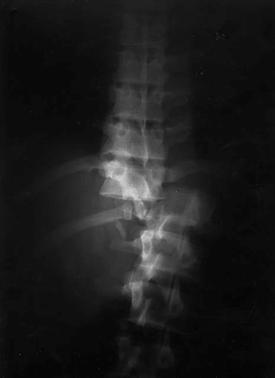

FRACTURA - LUXATIE T12 FRACTURA COMPLEXA DE COLOANA

VERTEBRALA LOMBARA